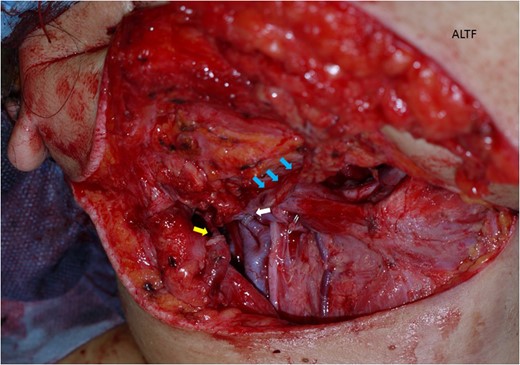

The surgical treatment for this patient involved tracheostomy, hemi-glossectomy and right-sided selective neck dissection when the patient was in her 28th week of pregnancy. Throughout the surgery, the patient was given a continuous intravenous infusion of ritodrine hydrochloride (100 mg in 500 ml) in order to provide tocolysis and prevent premature labour. A tracheotomy was preformed and the patient underwent a modified rapid sequence induction using fentanyl, thiopentone and rocuronium bromide. Anaesthesia was maintained with sevoflurane. A continuous fentanyl infusion provided analgesia and paralysis was maintained with boluses of atracurium besylate. Obstetricians were standing by for unexpected delivery. A cardiotocograph was used to monitor the foetus. The tissue defect was reconstructed with an antero-lateral thigh flap (Figs 3–5). The descending branch of lateral circumflex femoral artery was anastomosed to her right facial artery. One comitant vein was anastomosed to her external jugular vein in end-to-end fashion with a 2.5 mm microvascular anastomotic device. The other comitant vein was anastomosed in the same way to a branch of internal jugular vein with a 2.0 mm coupler. Heparin-saline solution (5000 units in 100 ml) was used to irrigate the anastomotic sites. Systemic heparin administration was not done during the operation. Lidocaine (2%) was used as vasodilator. Prostaglandin E1 was not administered. The operation took 7 h and 40 min. Blood loss was estimated to be 340 ml and no blood transfusion was required. Throughout the operation, no remarkable incidents were noted on the electronic foetal monitoring.

The antero-lateral thigh flap (ALTF) was transferred to her neck area. The descending branch of lateral circumflex femoral artery (blue arrows indicating) was anastomosed her right facial artery. A comitant vein was anastomosed to her external jugular vein in end-to-end fashion with a 2.5 mm microvascular anastomotic device (yellow arrow). The other comitant vein was anastomosed in the same way to a branch of internal jugular vein (white arrow).